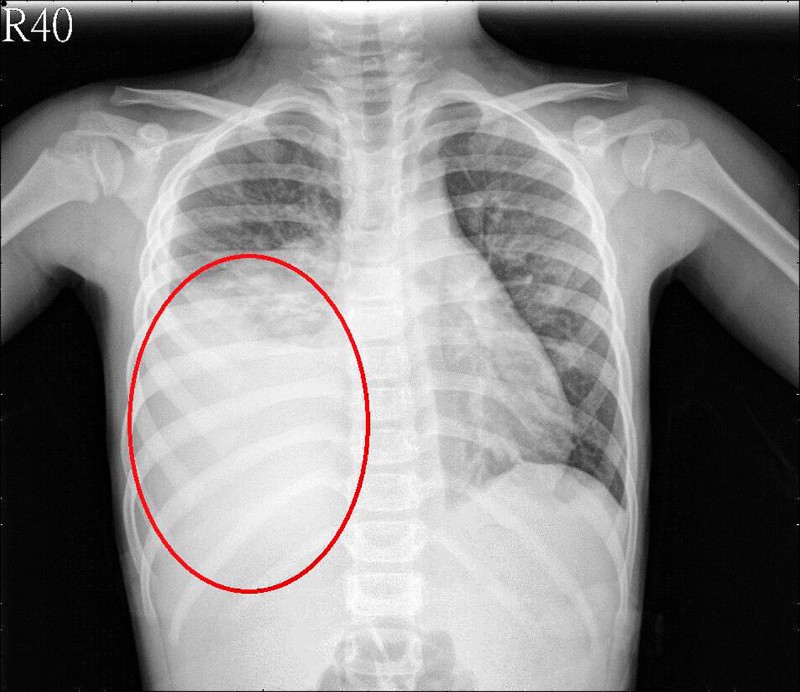

發燒、咳嗽是孩童生病時最常見的症狀,但5歲的陳小妹妹反覆高燒達40度並劇烈咳嗽,送醫後更發現大量肺積水,多達500CC,相當於1瓶可樂的量。經檢驗結果是黴漿菌感染所致,經抗生素治療,陳小妹妹住院3週後才退燒。醫師提醒,秋天是黴漿菌好發季節,且黴漿菌易致群體感染,學齡兒童要格外注意。

沈仲敏進一步指出,黴漿菌感染不一定會先出現高燒症狀,有時是久咳,可以持續3至4週;另外症狀還有寒顫、咽喉炎、嘔吐、腹痛、皮膚疹等;但如陳小妹妹一般,由黴漿菌引起肺積水的例子並不常見。